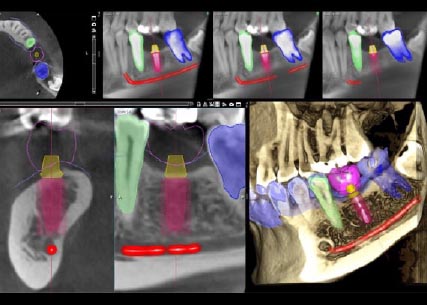

Diş hekimliğindeki dijital tarayıcılar, nerede ve nasıl kullanıldıklarına bağlı olarak farklı tiplerde sınıflandırılabilir: diş kliniklerinde, hastaya yönelik veya diş laboratuvarlarında, hastaya yönelik olmayan. Klinikler için diş tarama ekipmanı, CBCT veya intraoral tarayıcılar olarak kategorize edilebilir. Dental Konik ışın CT (CBCT) tarayıcılar, ağız bölgesinin X-ışınlarını almak için kullanılır ve intraoral tarayıcılar veya dental 3D tarayıcılar, hastalardan ağızlarında akışkan ölçü malzemesi ile oturmalarının istendiği geleneksel ölçü yönteminin yerini alır. CBCT ve intraoral tarama, tam protez tedavisi gibi geniş kapsamlı işlemler gerektiğinde birleştirilebilir.

İmplant diş hekimliğindeki dijital teknoloji, diş hekimlerinin restorasyonları, takma dişleri ve implantları nasıl planladıkları, tasarladıkları ve ürettikleri ve artık hastaları nasıl tedavi edebilecekleri konusunda benzersiz bir devrime neden oldu. Günümüzde implant diş hekimliğinde dijital bir iş akışı, manuel süreçleri neredeyse tamamen ortadan kaldırmıştır.

Örneğin diş hekimleri, implantı yerleştirirken, implant cerrahi kılavuz teknolojisini kullanarak implantoloji tedavisi için en son dijital diş hekimliği yeniliğine başvururlar. Diş hekimliğinde devrimin belirgin olduğu bir başka alan da dişsiz vakalardır: Bu hastalar için tedavi sonuçları tamamen şeffaftır ve tedavi tamamlandıktan sonra gülümsemelerinin tam olarak nasıl görüneceğini görebilirler. Sanal gülüş tasarımına yönelik teknolojiler, yalnızca diş hekimlerinin yaşamlarında devrim yaratmakla kalmaz, aynı zamanda hastalar için de devrim yaratır.